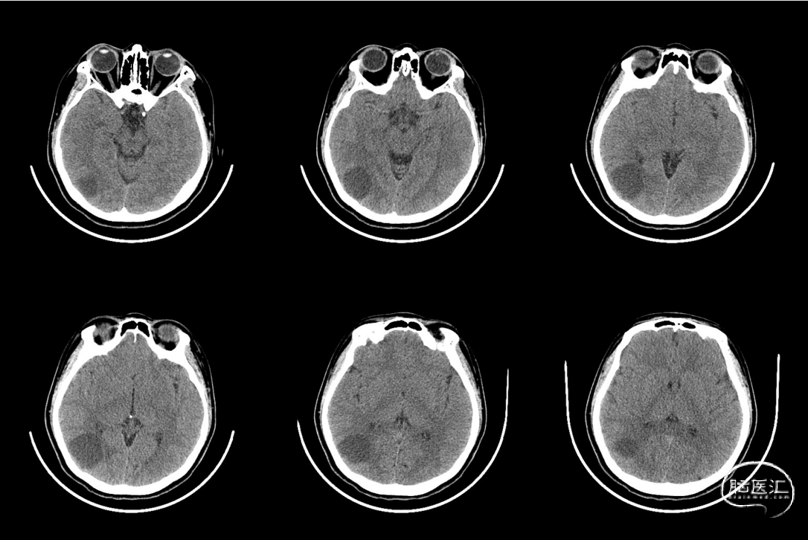

现病史:患者15天前无明显诱因下突发晕厥,伴有意识丧失,无四肢抽搐,无口吐白沫,无呼吸困难,数分钟后症状好转,神志转清,遂于当地医院查CT示“右侧颞叶囊性占位”。

2023-07-09 CT:右侧颞叶囊性占位,建议MR平扫+增强检查。